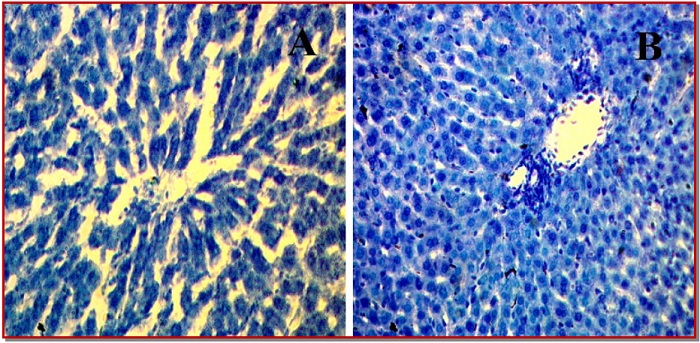

The present study investigates the pathological implications of parenchymal iron overload due to CCl4 treatment in liver dysfunction. Sixteen female rats were randomly divided into control and CCl4 treated groups. The serum levels of tramsaminases, malondialdehyde, advanced protein oxidation product, catalase, and reduced glutathione concentrations in the plasma and hepatic homogenate were determined. Moreover, histopathological changes in liver sections were investigated for inflammatory cell infiltration, fibrosis and iron overload. The administration of CCl4 resulted in increased liver marker enzymes activities and oxidative stress parameters mentioned above compared to control. Moreover, CCl4 administration also decreased antioxidant enzymes activities and increased inflammatory cell infiltration and fibrosis along with iron deposition in liver of rats. These findings indicate that CCl4 may induce hepatic fibrosis and inflammation during CCl4 induced liver injury via iron mediated oxidative damages.